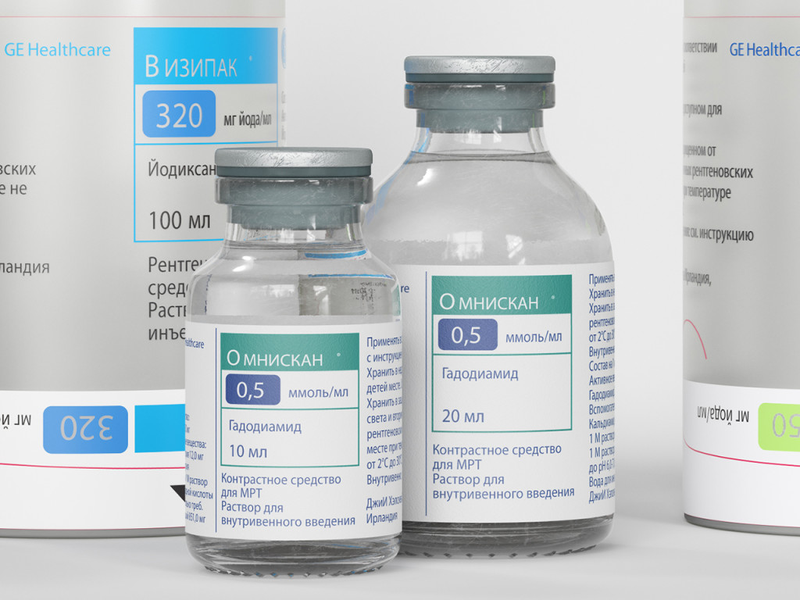

Рентгеноконтрастные Исследования Кишечника: Визуализация и Методики